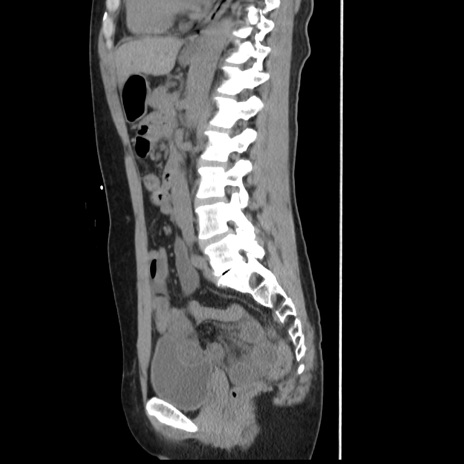

冠状断像

【症例】 50歳代女性

【主訴】 腹痛

【現病歴】前日生レバーを食べた。今朝に排便あり。 昼前に突然発症の腹痛を生じ、当院救急外来を受診した。

【既往歴】 子宮筋腫にてで子宮全摘後

【身体所見】 意識清明、腹部:平坦、軟、下腹部やや左を中心に圧痛・反跳痛あり、筋性防御あり

【データ】WBC 7800、CRP 0.07